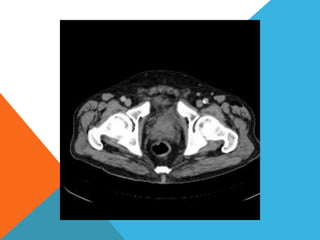

El paciente presentó síntomas de sangrado digestivo y pérdida de peso. Exámenes revelaron gastritis crónica asociada a H. pylori. Un tumor fue descubierto en una colonoscopia normal. La cirugía removió un tumor fibroide solitario, una rara neoplasia mesenquimal que usualmente crece lento y tiene bajo potencial de malignidad. El pronóstico después de la remoción quirúrgica es generalmente bueno.